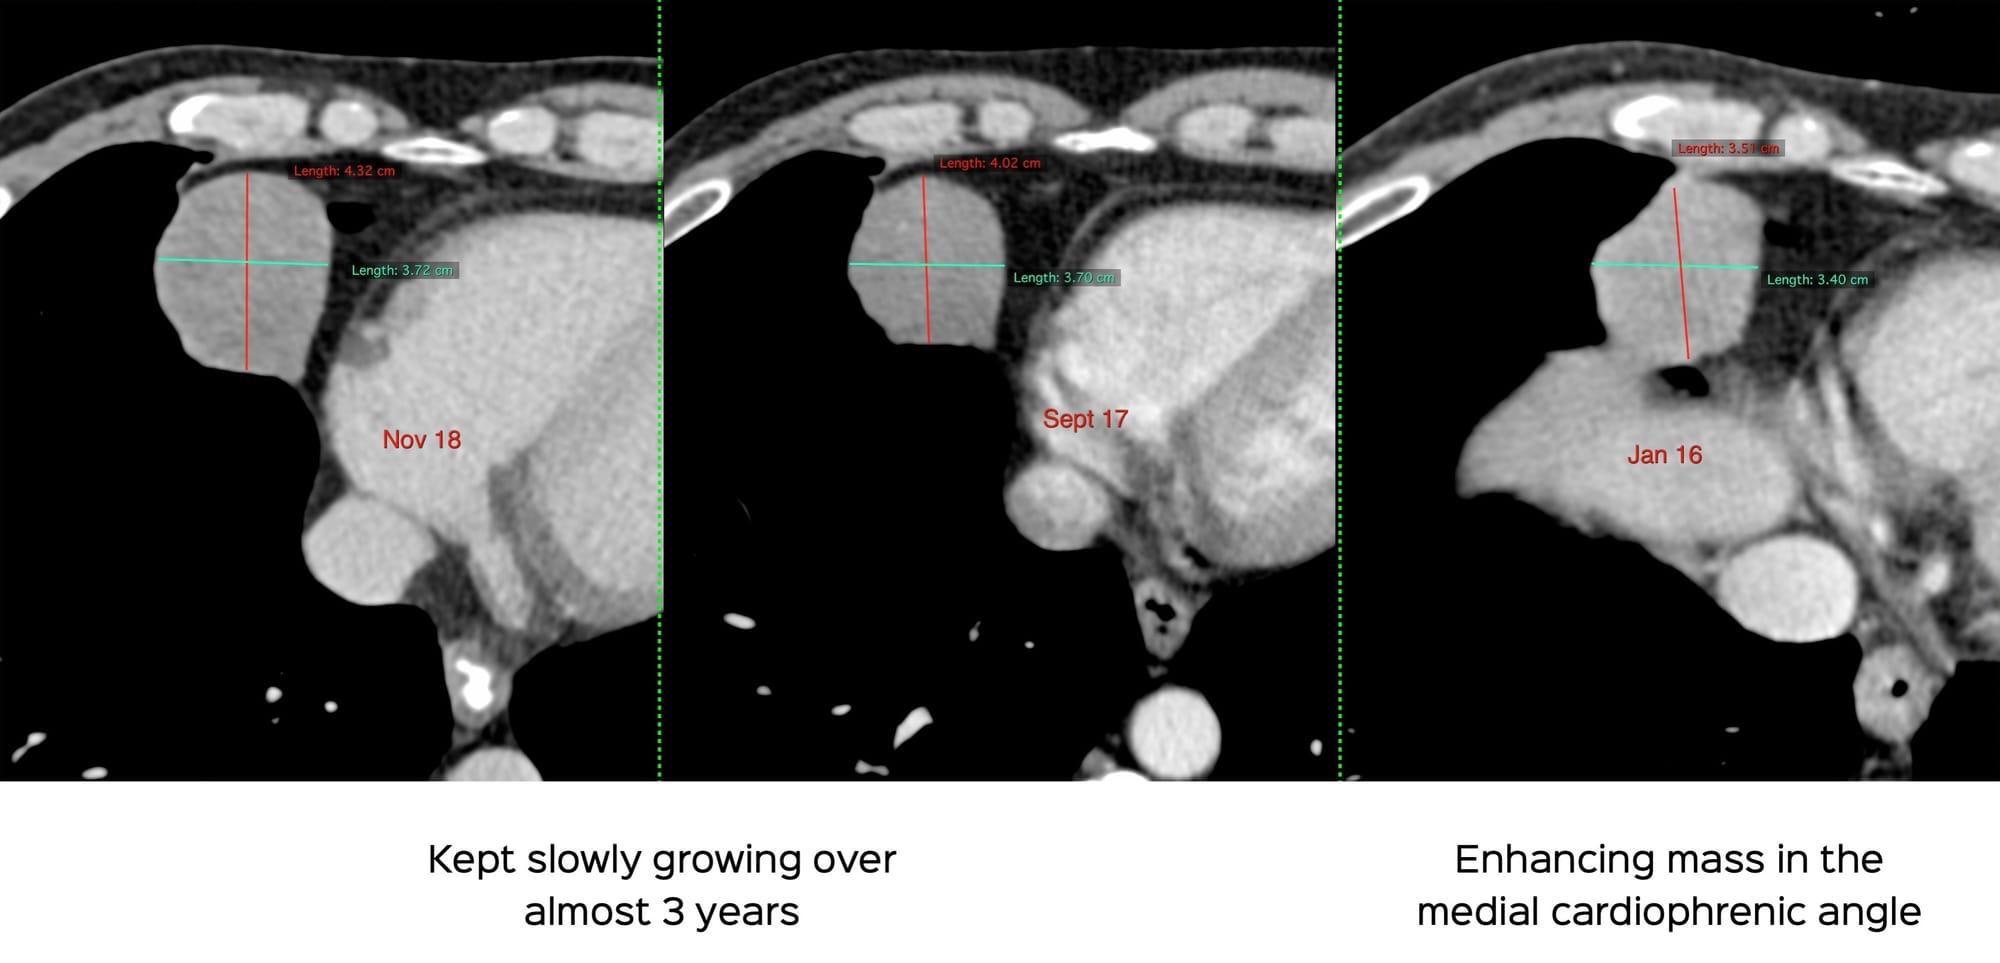

This 53-yrs old man came with an incidental, solid, enhancing medial cardiophrenic angle mass that kept growing over 8 years.

SFTPs can be diagnosed reliably on CT scan as solid enhancing, often incidental asymptomatic, pleural masses that grow slowly with minimal uptake on PET/CT, in the 50-70 years age group.